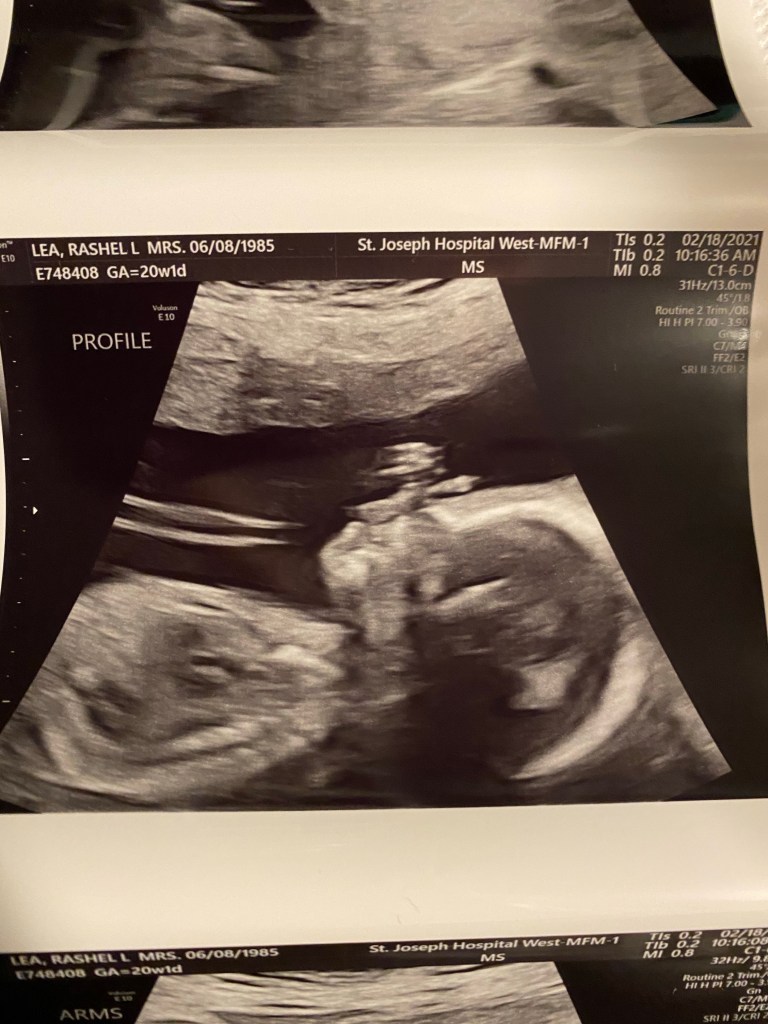

Today was the 20 week ultrasound at the MFM office at the hospital because now at 36 I’m an old pregnant lady. 😂 It was a long appointment and they looked at everything. We got mostly great news. He looks so perfect in there. He has sweet little lips and loves to move his arms and legs. I loved watching him wiggle around. He started out head down and we all know that makes me happy! But then he went transverse and then to breach! 😆 Obviously it’s still super early and he has lots of wiggle room to flip and turn and play. We could see all 4 chambers of the heart and his brain and spine they even looked at kidneys and eyes! Every square inch of this sweet boy we saw. The nurse practitioner did come in and let us know that it looks like we only have a two vessel umbilical cord. She said they normally have 3. The good news is because everything else seems perfect she said we shouldn’t really be worried. I will have to now have more appointments to watch and monitor his growth. So I will be going back every 4 weeks for a growth scan. The obvious perk is we will get to see his sweet little face more often!!! It will always amaze me how fast they grow and how perfect he looks. The screen makes him look SO big but in reality he was a whopping 12oz! A whole soda can in there. Seeing him wiggle and grow makes me love him even more and I can’t wait to see his sweet little face in 20ish weeks. Leaf was so sweet on the phone and talked about his baby brother coming. It’s so special to help a family have a baby but, it’s also so exciting to help make Leaf a big brother!!! I’m sure like any older sibling he’s going to be shocked that a new baby is there and all his normal attention has to be shared now but I just know he’s going to do great.